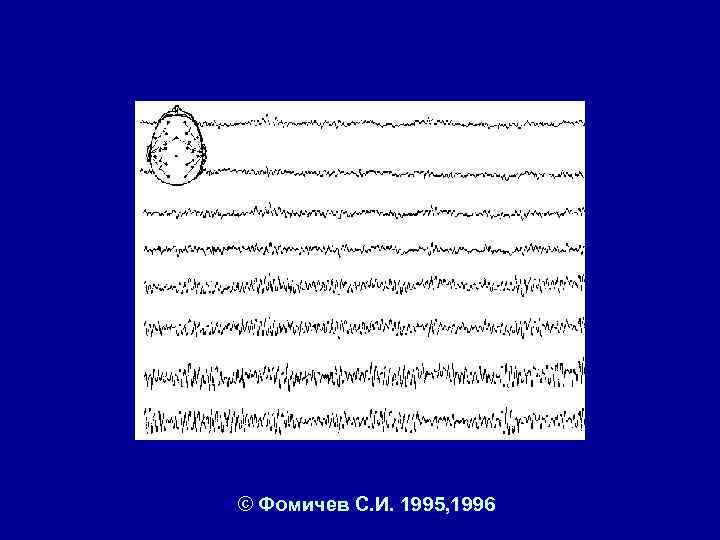

© Фомичев С. И. 1995, 1996

© Фомичев С. И. 1995, 1996